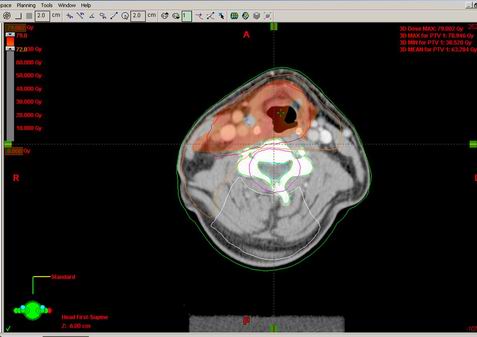

53-letý Z.T.

Karcinom hypofaryngu, recesus piriformis l.dx T2 N2b M0, spinoca

Kurativní RT – konvenční frakcionace

Zakreslení struktur:

DVH:

Dávka > 40Gy:

Dávka > 45 Gy:

Dávka > 54 Gy:

Dávka > 60 Gy:

Dávka > 72 Gy: